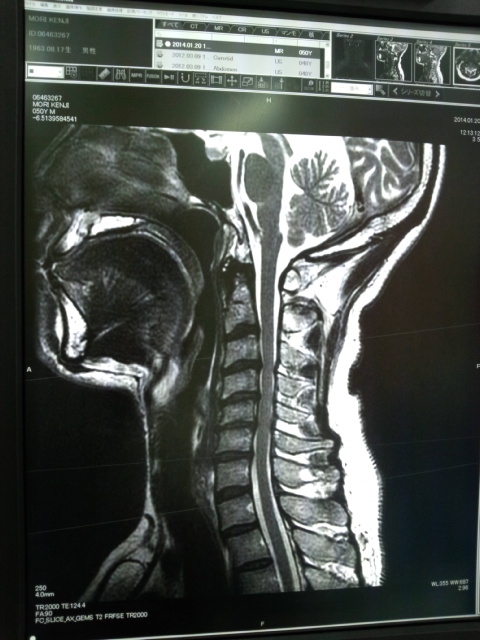

隼小僧@頚椎症神経根症  - 14/2/17(月) 7:58 -

乗り手も首の症状が回復せず冬眠しております・・・。

春になったら、暖かくなったら回復するのかな?

通う病院変えたほうが良いのかな?

と、思う今日この頃。。。

添付画像

【20140120130422.jpg : 183.7KB】